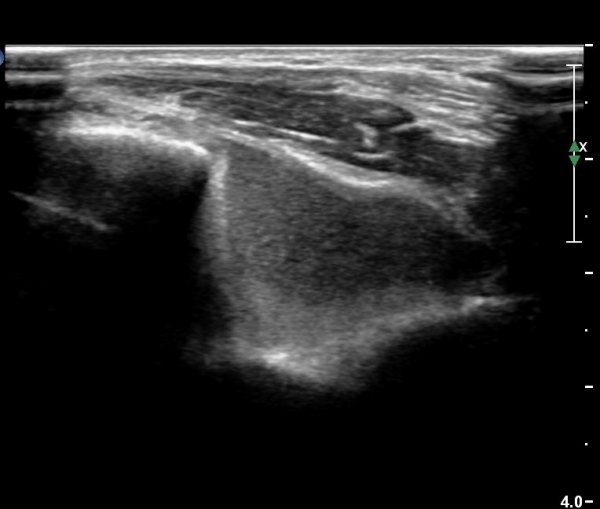

¿Ü»ó°ú¿Í ½ÅÀü°Ç Á¾´Ü¸é°Ë»ç¿¡¼­ ƯÀÌ ¼Ò°ß º¸ÀÌÁö ¾ÊÀ½(»çÁø 1)

³»»ó°ú¿Í ±¼°î°Ç Á¾´Ü¸é°Ë»ç¿¡¼­ ƯÀÌ ¼Ò°ß º¸ÀÌÁö ¾ÊÀ½(»çÁø2).